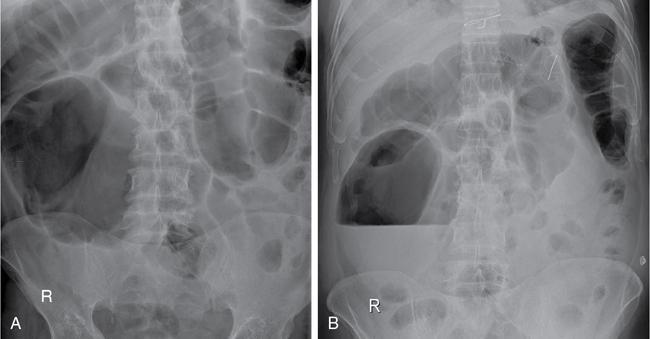

Plain abdominal radiograph

Ultrasonography (USG)

Contrast enema

Technique